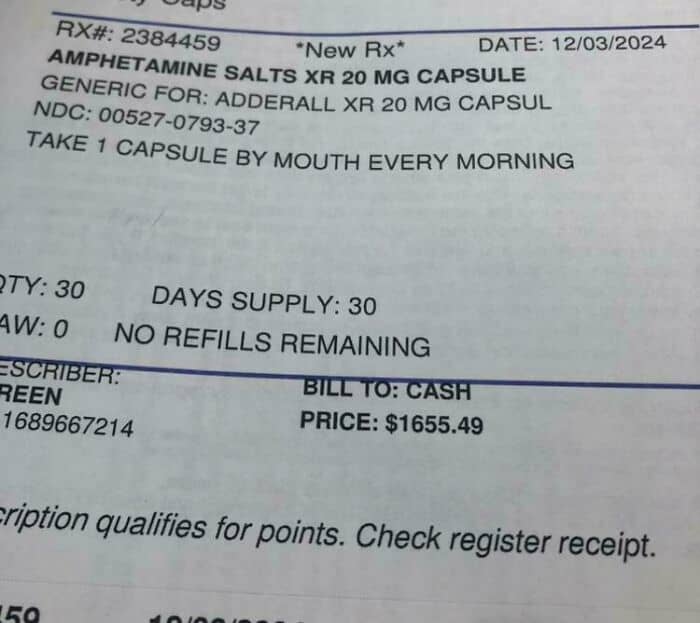

#63 How Much My Kid’s 30 Day Supply Of Generic Adderall Would Have Cost Without Insurance. ‘Murica